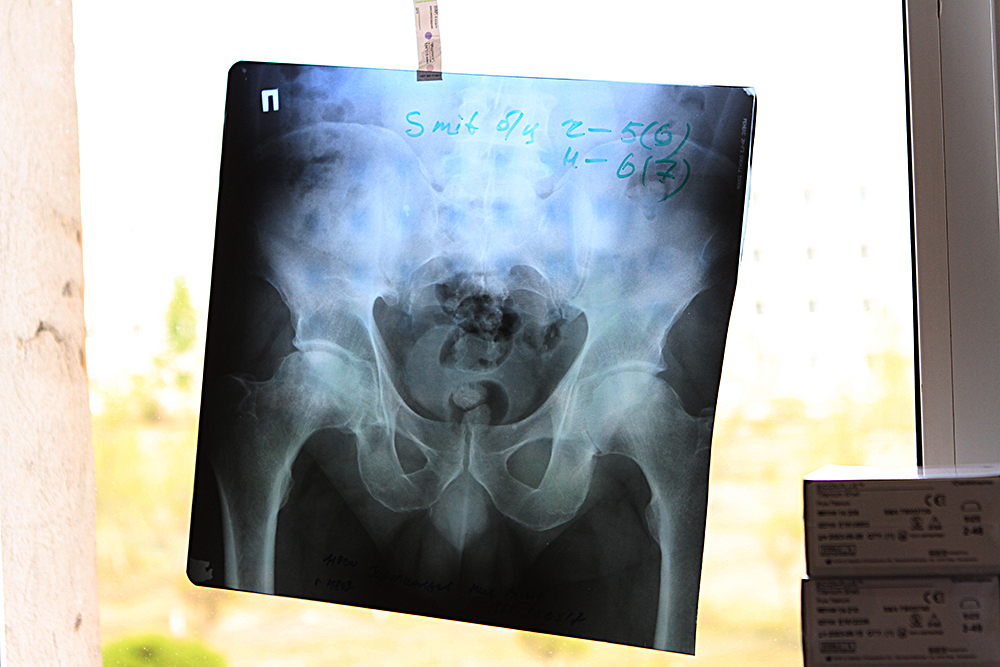

Министр Давыдов провел операцию на "Фестивале хирургов" в Краснокаменске (фото Анны Хвостовой)